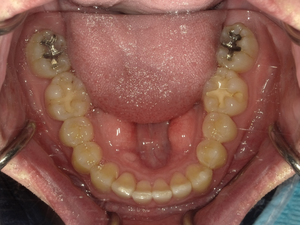

☆before→after☆◯ご相談内容:歯の叢生◯矯正の種類:マウスピース型矯正「インビザラインGO」◯治療期間:10週間◯治療費用:44万円(税込)